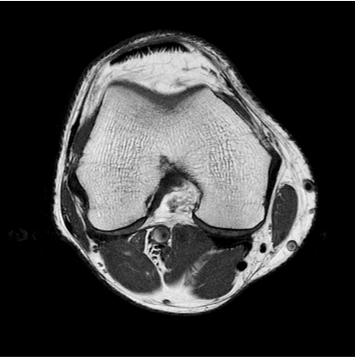

384 x 256 (2 NEX)

1:30 minstandard

384 x 256 (4 NEX)

2:59 minIAI (Innovative AI)

384 x 256 (2 NEX)

1:28 minReduced Scan Time

384 x 256 (2 NEX)

1:29 min촬영속도의 혁신, IAI

기존

IAI

IAI는 AI Deep learning을 통해 기존 장비의 촬영 프로토콜을 최적화합니다.

기존 프로토콜 대비 촬영 시간을 50% 단축시키며, 이미지 퀄리티는 증가합니다.